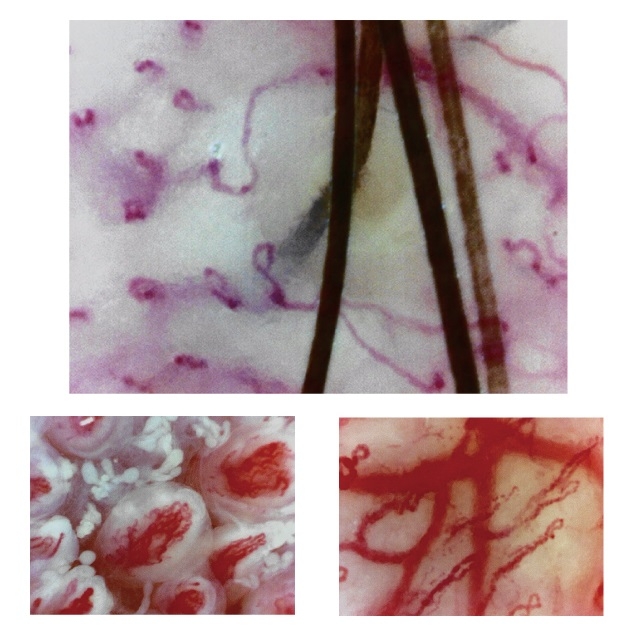

毛細血管スコープ Bscan-ZD 研究セット|顕微鏡・光学機器|製品 大画面の9インチモニター付きの「新品未使用品」の血流スコープです。(98,553円の商品をヤフオク専用の特別価格で販売しています。)他の商品は倍率が低いため、血流が見えにくいという欠点がありました。そのため、このモデルに買い換えた方も中にはいらっしゃっいました。この商品は市販品の中では「最も高倍率」の血流スコープになります。スマホのカメラに例えると「望遠レンズ」になりますので、大きく見ることができます。また、血流スコープの見やすさはレンズの大きさに比例します。以前、購入された方から「20万円する商品よりもよく見える!」との感想を頂きましたが、その理由は、鏡筒(レンズ)が大きいからです。安いスマホのカメラは画質が悪く、iPhoneのカメラの画質がいい理由の1つは、レンズが大きいからです。他社の商品よりも、くっきりと大きく写りますので、血流の流れを鮮明に確認する事ができます。1枚目から4枚目の商品の写真は、仕様変更前の写真になります。商品の改良で、下部のレンズが少し大きくなり、更に見やすくなりました。お送りする商品の写真は5枚目~9枚目をご確認ください。付属のモニターでも「ipad mini」より大きな画面で見ることができます。また、テレビのRCA端子に接続して、大画面テレビで見ることも可能です。(コードを購入する必要はありません。)日本語の説明書が付いていますので、接続に不安がある方もご安心下さい。ピントを合わせると、かなり鮮明に写りますので、運動後に確認をすると、血流がかなり早くなっていることもしっかりと確認できます。また、高倍率のため、ゴースト血管のチェックもできます。実際の使い方ですが、薬指の爪の甘皮の部分にオイルを付けて、毛細血管を観察します。オイルはどのオイルでも問題なく見ることができますので、家庭にあるオリーブオイルや食用油をご利用下さい。持ち運びをする時は、付属のアルミニウムケースをご使用下さい。なお、テレビで見るときは白黒になりますが、カラーで見たい方は変換器を購入すると、カラーで見ることができます。円安でかなり仕入れ価格が上がっていますが、価格をかなり抑えて販売していますので、よろしくお願い致します。